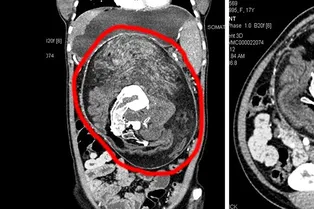

Дикий медицинский случай: как в животе девушки нашли близнеца-паразита